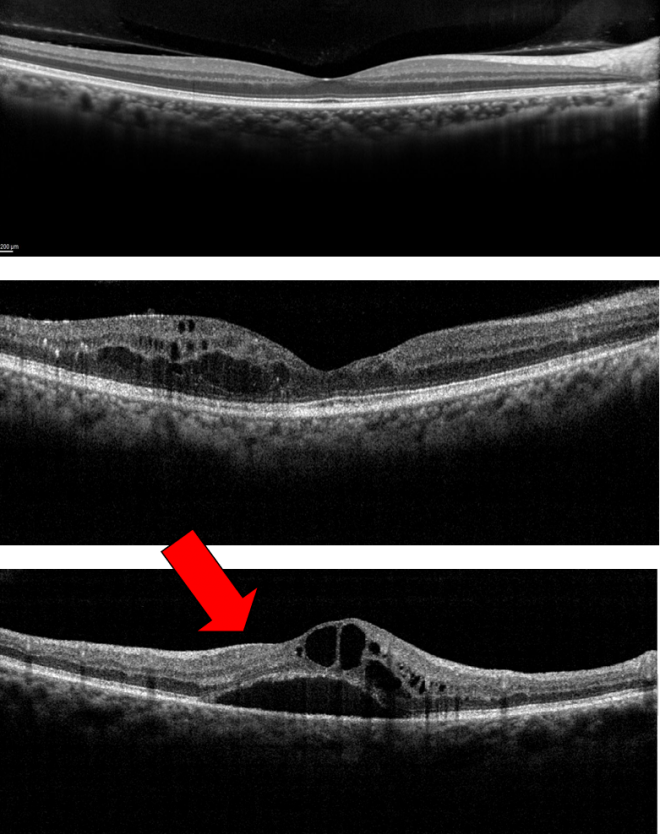

From www.researchgate.net

Scans of a NMOSDON eyes with and without microcystic macular edema Can Eye Strain Cause Macular Edema Macular edema is often caused by leakage of fluid from damaged or abnormal blood vessels in the retina. Macular edema happens when fluid builds up in the macula, causing swelling. Learn about other causes of blurry vision. Macular edema is caused by pockets of fluid (usually leakage from damaged blood vessels) swelling up in the macula. This fluid causes the. Can Eye Strain Cause Macular Edema.